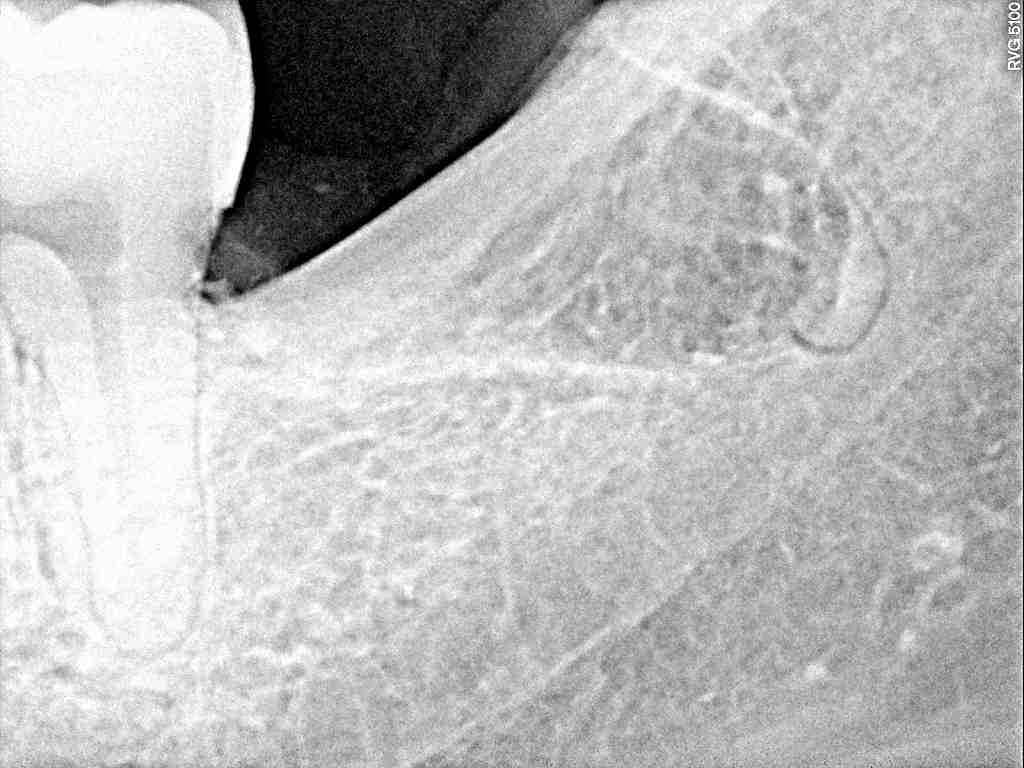

左下の奥の親不知の難抜歯 横に生えていますがこのタイプは抜きやすい歯になります|お知らせ |広島市安佐南区の歯科医院 左下の奥の親不知の難抜歯 横に生えていますがこのタイプは抜きやすい歯になります トップ お知らせ・ブログ お知らせ 左下の奥の親不知の難抜歯 横に生えていますがこのタイプは抜きやすい歯になります 左下の奥の親不知の難抜歯 横に生えていますがこのタイプは抜きやすい歯になります 問題の歯になります 虫歯にもなっていました デンタルレントゲンになります 根尖部は破折しました 根尖部を除去しました 縫合して終了となります 綺麗に取れました Web診療予約 初めての方へ 選ばれ続ける理由 院内設備について 歯が痛いしみる一般歯科 歯がぐらぐらする歯周病 健康な歯を保ちたい予防歯科 子供の虫歯予防をしたい小児歯科 銀歯をセラミックに審美歯科 白い歯を目指しませんか?ホワイトニング 矯正専門医がいるので安心矯正歯科 抜けた歯を補いたいインプラント・入れ歯 医院案内 スタッフ紹介 メリィハウス歯科クリニックオフィシャルホームページ ラベンダー歯科クリニックオフィシャルホームページ お知らせ・ブログ ホーム 診療科目 一般歯科 歯周病治療 予防治療 小児歯科 審美治療 ホワイトニング 矯正歯科 入れ歯・インプラント マウスピース矯正 初めての方へ 院長・スタッフ 設備紹介 医院案内・アクセス メニューを閉じる